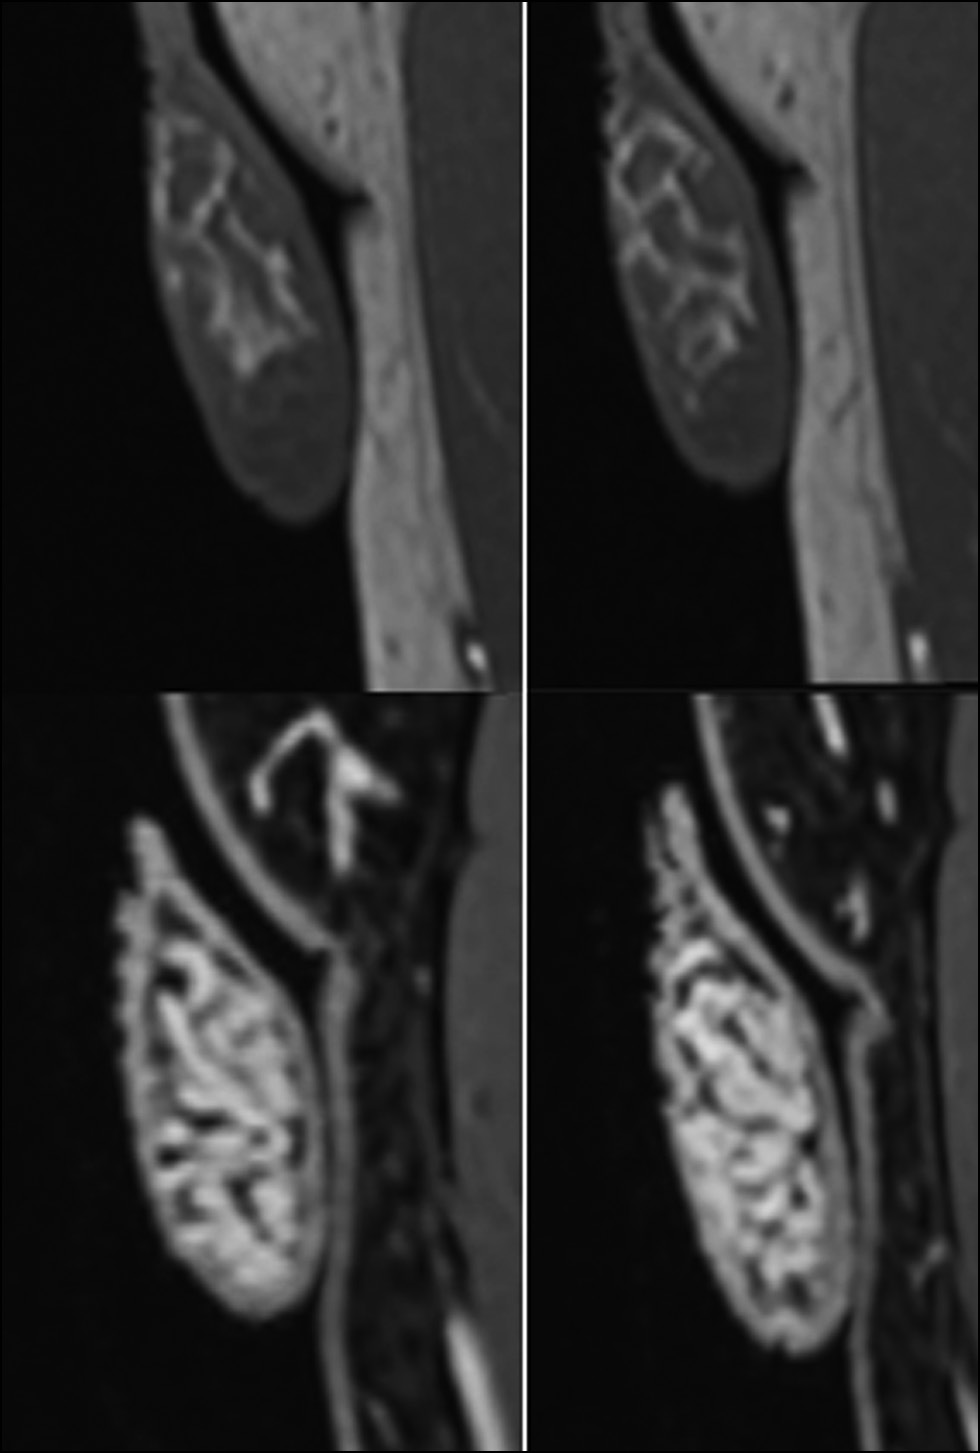

В данной области отмечено усиление контрастности патологического очага, характеризующееся септальным паттерном, особенно в периферической области уровня верхнего полюса. Отёчность была вызвана увеличением придатка яичка, обусловленным левосторонним варикоцеле при наличии тонкого слоя гидроцеле (рис. 6–8).

Рис. 6. Наблюдается усиление контрастности патологического очага в исследуемой области, особенно в верхнем полюсе. В Т1-режиме область даёт изоинтенсивный сигнал по сравнению с остальными тканями яичка. Выделены гиперинтенсивные участки кровоизлияний. После введения контрастного вещества (например, гадолиния) в исследуемой области выявлено отсутствие сосудов с характерным ореолом насыщенности по периферии патологического очага.

Рис. 7. Две группы изображений ишемизированной области левого яичка на разных уровнях. Верхние и нижние изображения получены в режимах STIR и T2 соответственно.

В рассматриваемом случае область ишемии овальной формы в левом яичке давала гипоинтенсивный сигнал, наблюдалось усиление контрастности патологического очага в исследуемой области, особенно в верхнем полюсе [5].

В Т1-режиме область давала изоинтенсивный сигнал по сравнению с тканями яичка. Были выделены гиперинтенсивные участки кровоизлияний. После введения контрастного вещества в исследуемой области выявлено отсутствие сосудов с выраженным ореолом насыщенности по периферии патологического очага.